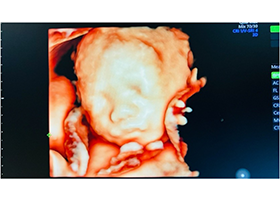

問診・血圧測定・体重測定・尿検査・超音波検査・内診などを行い、母児の健康診査を行います。 - 遺伝カウンセリング